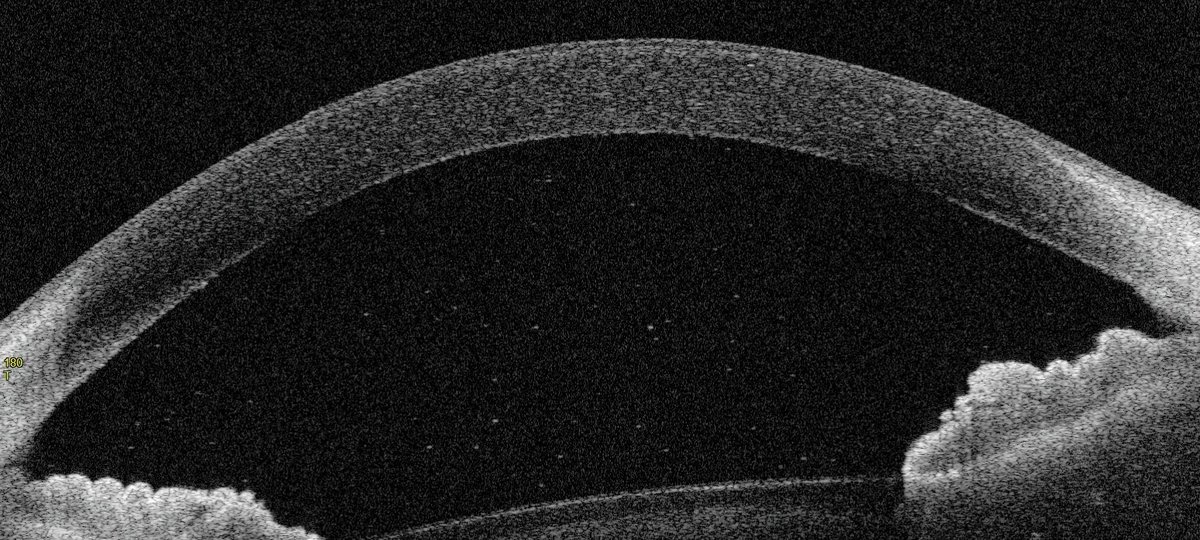

Juvenile idiopathic arthritis (JIA) is the most common form of arthritis in children under the age of 16, affecting around one in every 1,000 children in the UK. Approximately 30% of patients with JIA also develop uveitis – an inflammatory condition of the eye that is potentially sight-threatening.

The new research provides a clearer picture of the immune cells involved in JIA-associated uveitis.

In this study, the team combined blood data with these rare eye samples to explore disease mechanisms more directly. They first compared blood samples from children with arthritis alone (JIA) and children with both arthritis and eye inflammation (JIA-uveitis). They then identified and counted various types of immune cells in the eyes of patients.

The researchers observed that B-cells were consistently present in increased numbers in the blood and inflamed eyes of JIA-uveitis patients.